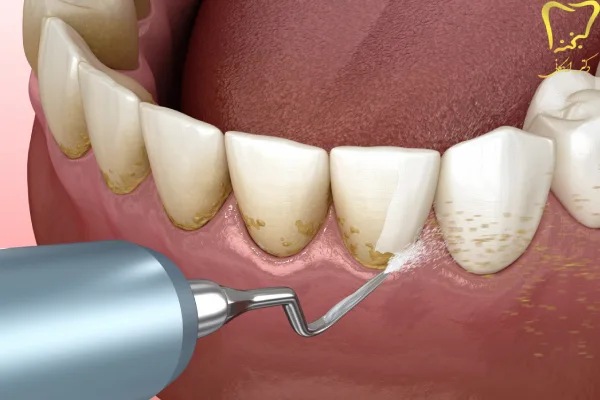

جرمگیری دندان که در انگلیسی به آن Teeth Scaling گفته میشود، یکی از روشهای مؤثر برای پاکسازی عمیق دندانها و لثههاست. این فرایند که گاهی با نام بروساژ دندان نیز شناخته میشود، به از بین بردن پلاک و جرم (تارتار) از سطح دندان و زیر خط لثه کمک میکند.

بروساژ فک دو مرحله پیوسته و مکمل یکدیگر می باشند. در واقع هر دو یک کار را انجام می دهند. جرمگیری دندان تمامی رسوب هایی که به مرور زمان بر روی دندان ها جمع شده اند را پاکسازی می کند و از بین می برد.

این میکروب ها براحتی و کم کم بر روی دندان ها می چسبند. در ابتدا این لایه رسوب نرم و قابل شستشو و از بین بردن می باشند. اما به مرور زمان حتی بعد از گذشت یک یا دو روز این لایه ها اگر پاکسازی نگردند تبدیل به یک رسوب بسیار سخت می شوند. این رسوب ها سخت شده اند و دیگر با مسواک پاک نمی شوند و نیازمند جرمگیری دندان دارند.

جرم گیری و بروساژ کامل دندان می تواند جرم موجود در بالا و زیر لثه را از بین ببرد. گاهی رسوب های زیر لثه، رنگی سیاه و یا مایل به قهوه ای دارند. این رسوب ها در تحلیل ریشه دندان و لثه بسیار اثرگذار می باشند.

استفاده از ابزارهای جرم گیری:

دندانپزشک از ابزارهایی مثل ابزارهای دستی، اولتراسونیک یا لیزر برای از بین بردن جرم و پلاک دندانی کمک می گیرد.